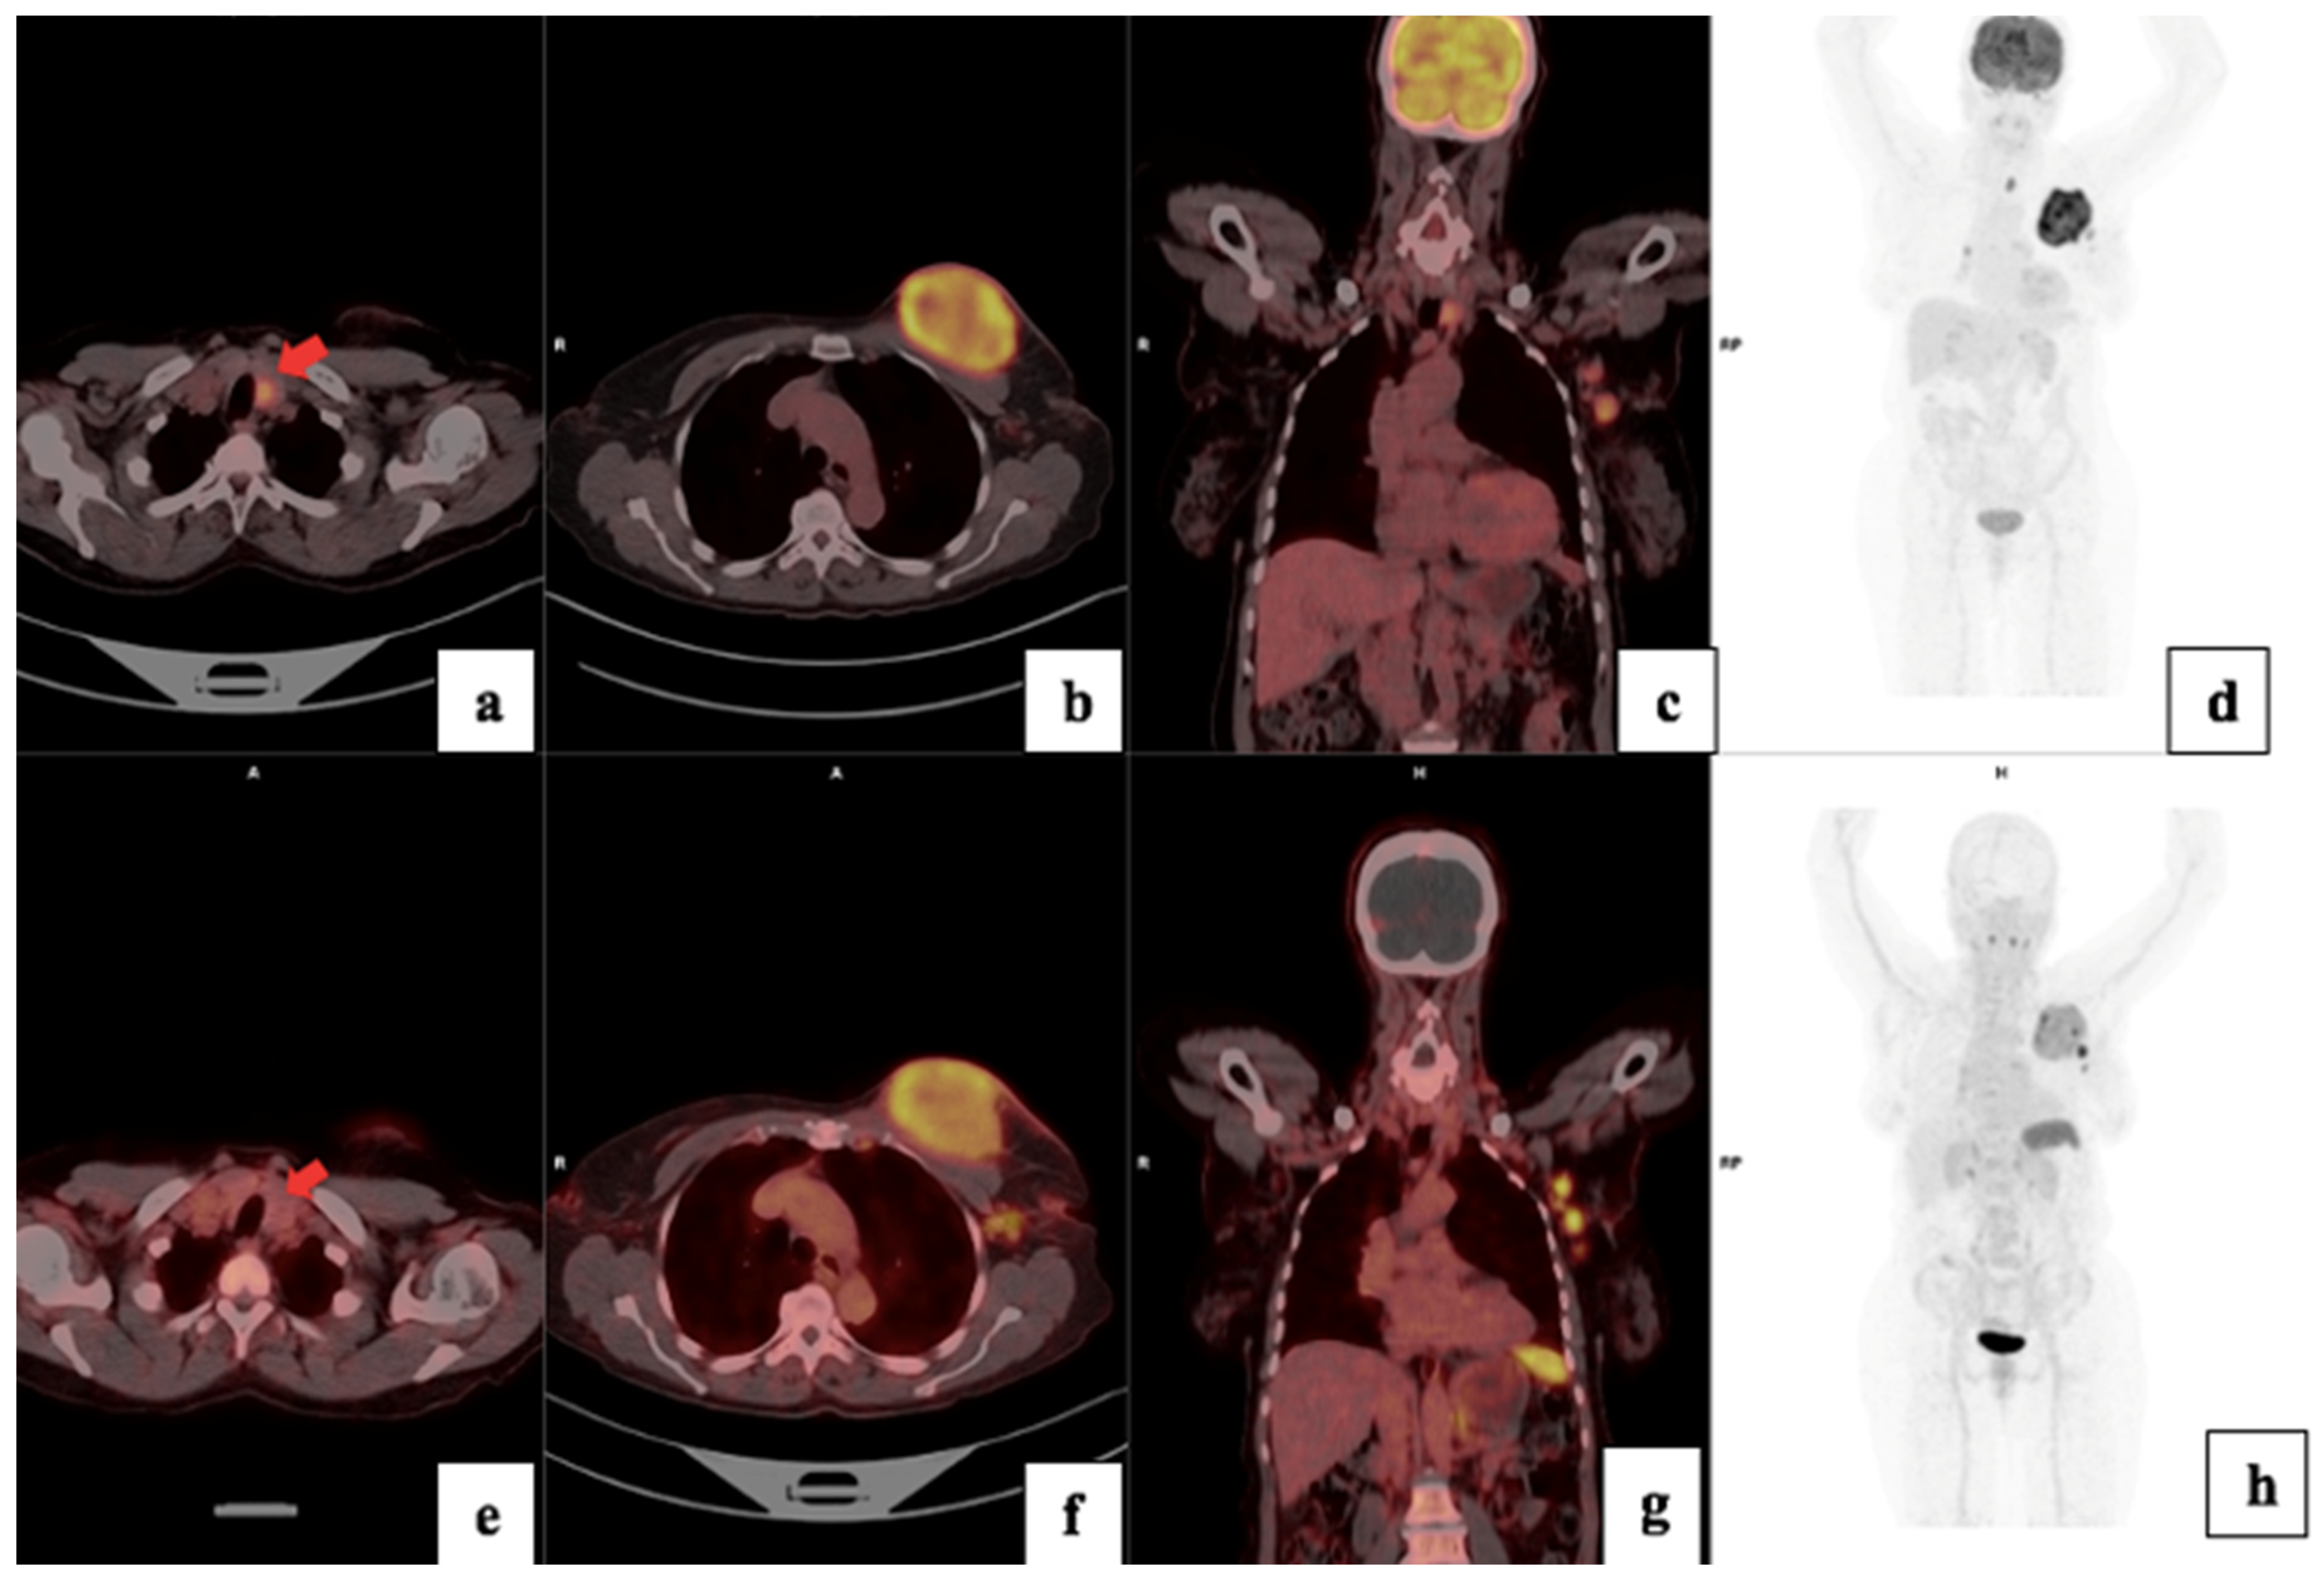

Figure 6.

18F-FDG (a–d) and 68Ga-Pentixafor (e–h) images showing increased uptake in the left breast primary (b,f) and left axillary lymph nodes (c,g) in a a 64-year-old female with T3N1M0 triple-negative invasive ductal carcinoma of the left breast. The primary tumour exhibited a Ki67 index of 90% and an SUVmax of 7.26, on 68Ga-Pentixafor and 20.79 on 18F-FDG. Notably, 18F-FDG showed high uptake in a benign thyroid lesion (a), which was negative using Pentixafor as indicated by the arrows (e).

In addition, because of the less intense physiological uptake of 68Ga-Pentixafor in the brain, this novel tracer allows for better visualization of metastasis in the skull and brain, as demonstrated in Figure 6. This is in agreement with findings by Buck et al. [25]. As the brain is an obligate user of glucose, there is a high physiological uptake of FDG, which may obscure both intracranial and skull lesions. However, 68Ga-Pentixafor, similar to [18F]-FDG, also accumulated in reactive lymph nodes, and therefore, the biopsy of suspicious lymph nodes remains invaluable for confirmation of metastatic spread, especially in areas outside the normal/expected lymphatic drainage of the breast. 68Ga-Pentixafor missed skeletal metastasis in the spine in two patients likely due to the high physiological bone marrow accumulation of this tracer; an example is shown in Figure 9. The high but variable physiological uptake on 68Ga-Pentixafor is due to CXCR4 expression on hematopoietic stem cells and progenitor cells in the bone marrow [26]. Further, it is possible that the high bone marrow accumulation of 68Ga-Pentixafor is attributed to an immune response triggered by stress signals originating from peripheral tissues, which subsequently activate the bone marrow [26]. Solid tumors, including breast cancer, induce a state of chronic inflammation that causes myelopoiesis in the bone marrow.